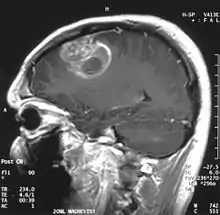

| Coronal MRI with contrast of a glioblastoma in a 15-year-old male | |